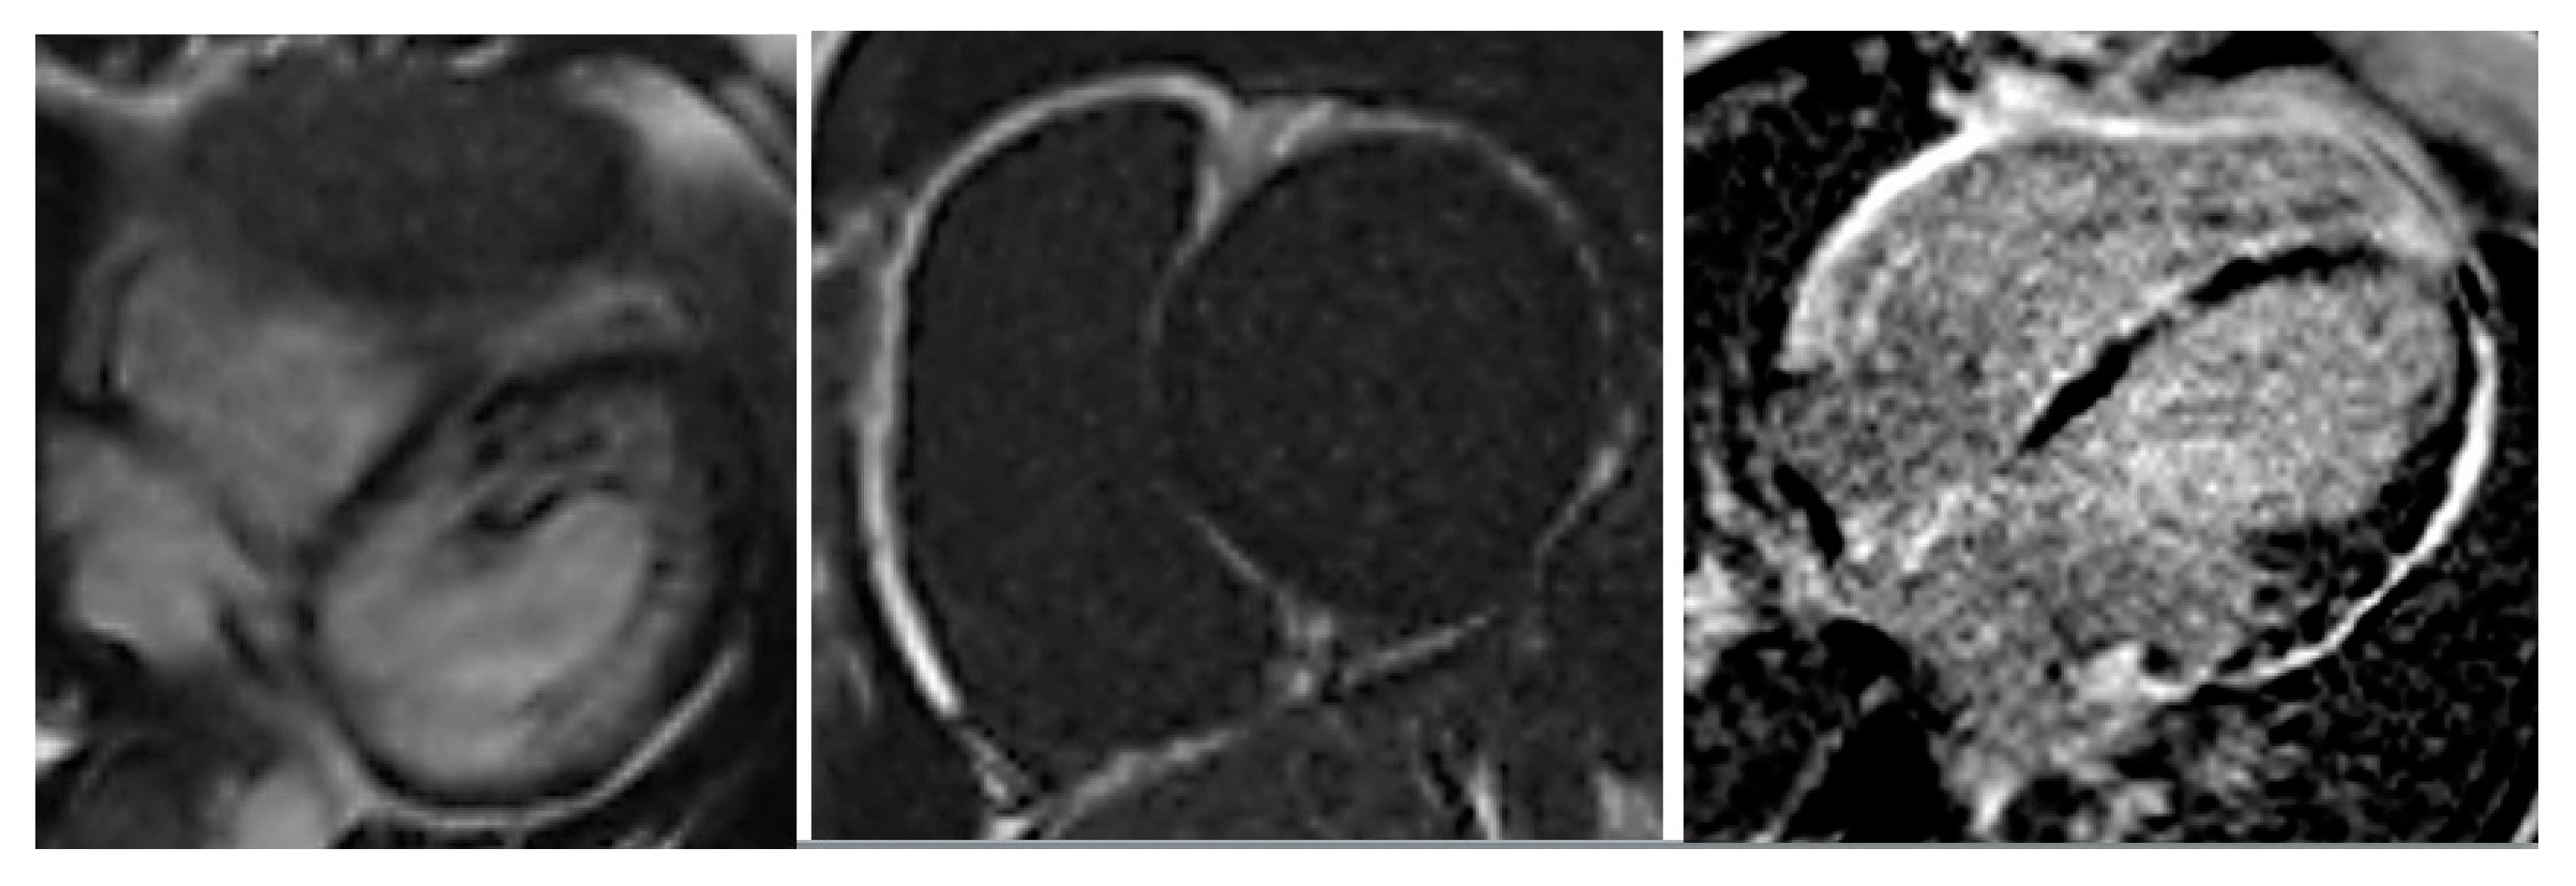

EchoCG showed left and right ventricular dilatation (EDD 6.2 and 4.0 cm, respectively) and diffuse reduction of LV contractility (EF 37%), with normal VTI 15.4 cm. Multiple pseudochordae were visualized in LV, but there were no convincing echocardiographic signs of LVNC. To verify the presence of LVNC, the patient underwent cardiac computed tomography (CT); coronary arteries were intact, LV myocardium had increased trabecularity in the apical-lateral and posterior walls, and the ratio of noncompact and compact layers was 3:1. Zones of late contrast agent accumulation in the middle and subendocardial layer of LV were visualized. In addition, a myocardial radionuclide perfusion scan was performed, which showed indicator inclusions in LV myocardium with diffusely nonuniform distribution, with areas of relative indicator hypoaccumulation more pronounced in the IVS and apical and middle sections of LV anterior wall. Such pattern is nonspecific, but typical for myocardial diseases. Cardiac MRI CD-disk was reanalyzed by Professor Sinitsyn. MRI findings were not typical for postinflammatory changes or DCM; the picture of ARVC (according to TFC-2010 [2]) in combination with LVNC (Figure 3) was found. Thus, the presence of LVNC was verified by cardiac CT and MRI.

Figure 3.

Cardiac MRI: left ventricular (LV) end-diastolic diameter (EDD) 66 mm, LV end diastolic volume EDV 243 mL, EF 41%, RV EDD 48 mm, RV EDV 115 mL/m2, EF 25%, areas of hypo/diskinesia of the front wall of RV, in the early and late phases—subepicardial areas of late gadolinium enhancement throughout LV, in IVS from the side of RV and along the walls of RV.